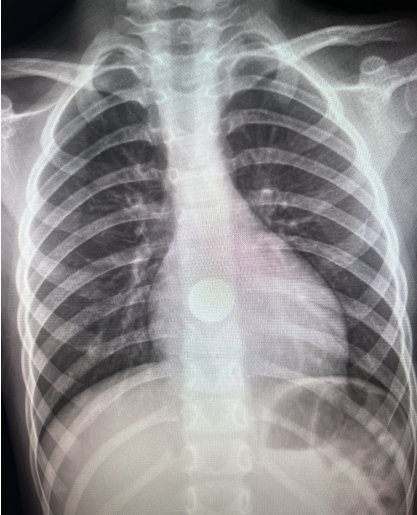

第一例患者,女性,5岁,吞入硬币

1、X线检查是诊断食管异物的重要方法之一,特别适用于金属等不透光的异物或大块致密骨质。方法是通过颈胸部正、侧位片来确定异物的大小、形态和部位。特点:操作简单,成本低廉,但可能无法检测到某些非金属或小型异物。